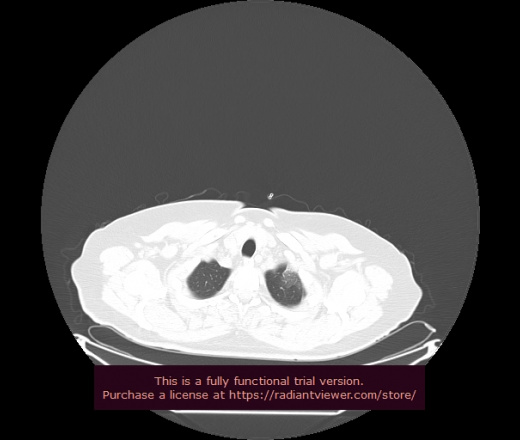

Уважаемые коллеги, если имеется интерес, сможете ли Вы спрогнозировать дальнейшее +-одинаковое течение процесса у 4 данных разных пациентов? Зацепиться где-то можно очень просто, где-то нельзя.